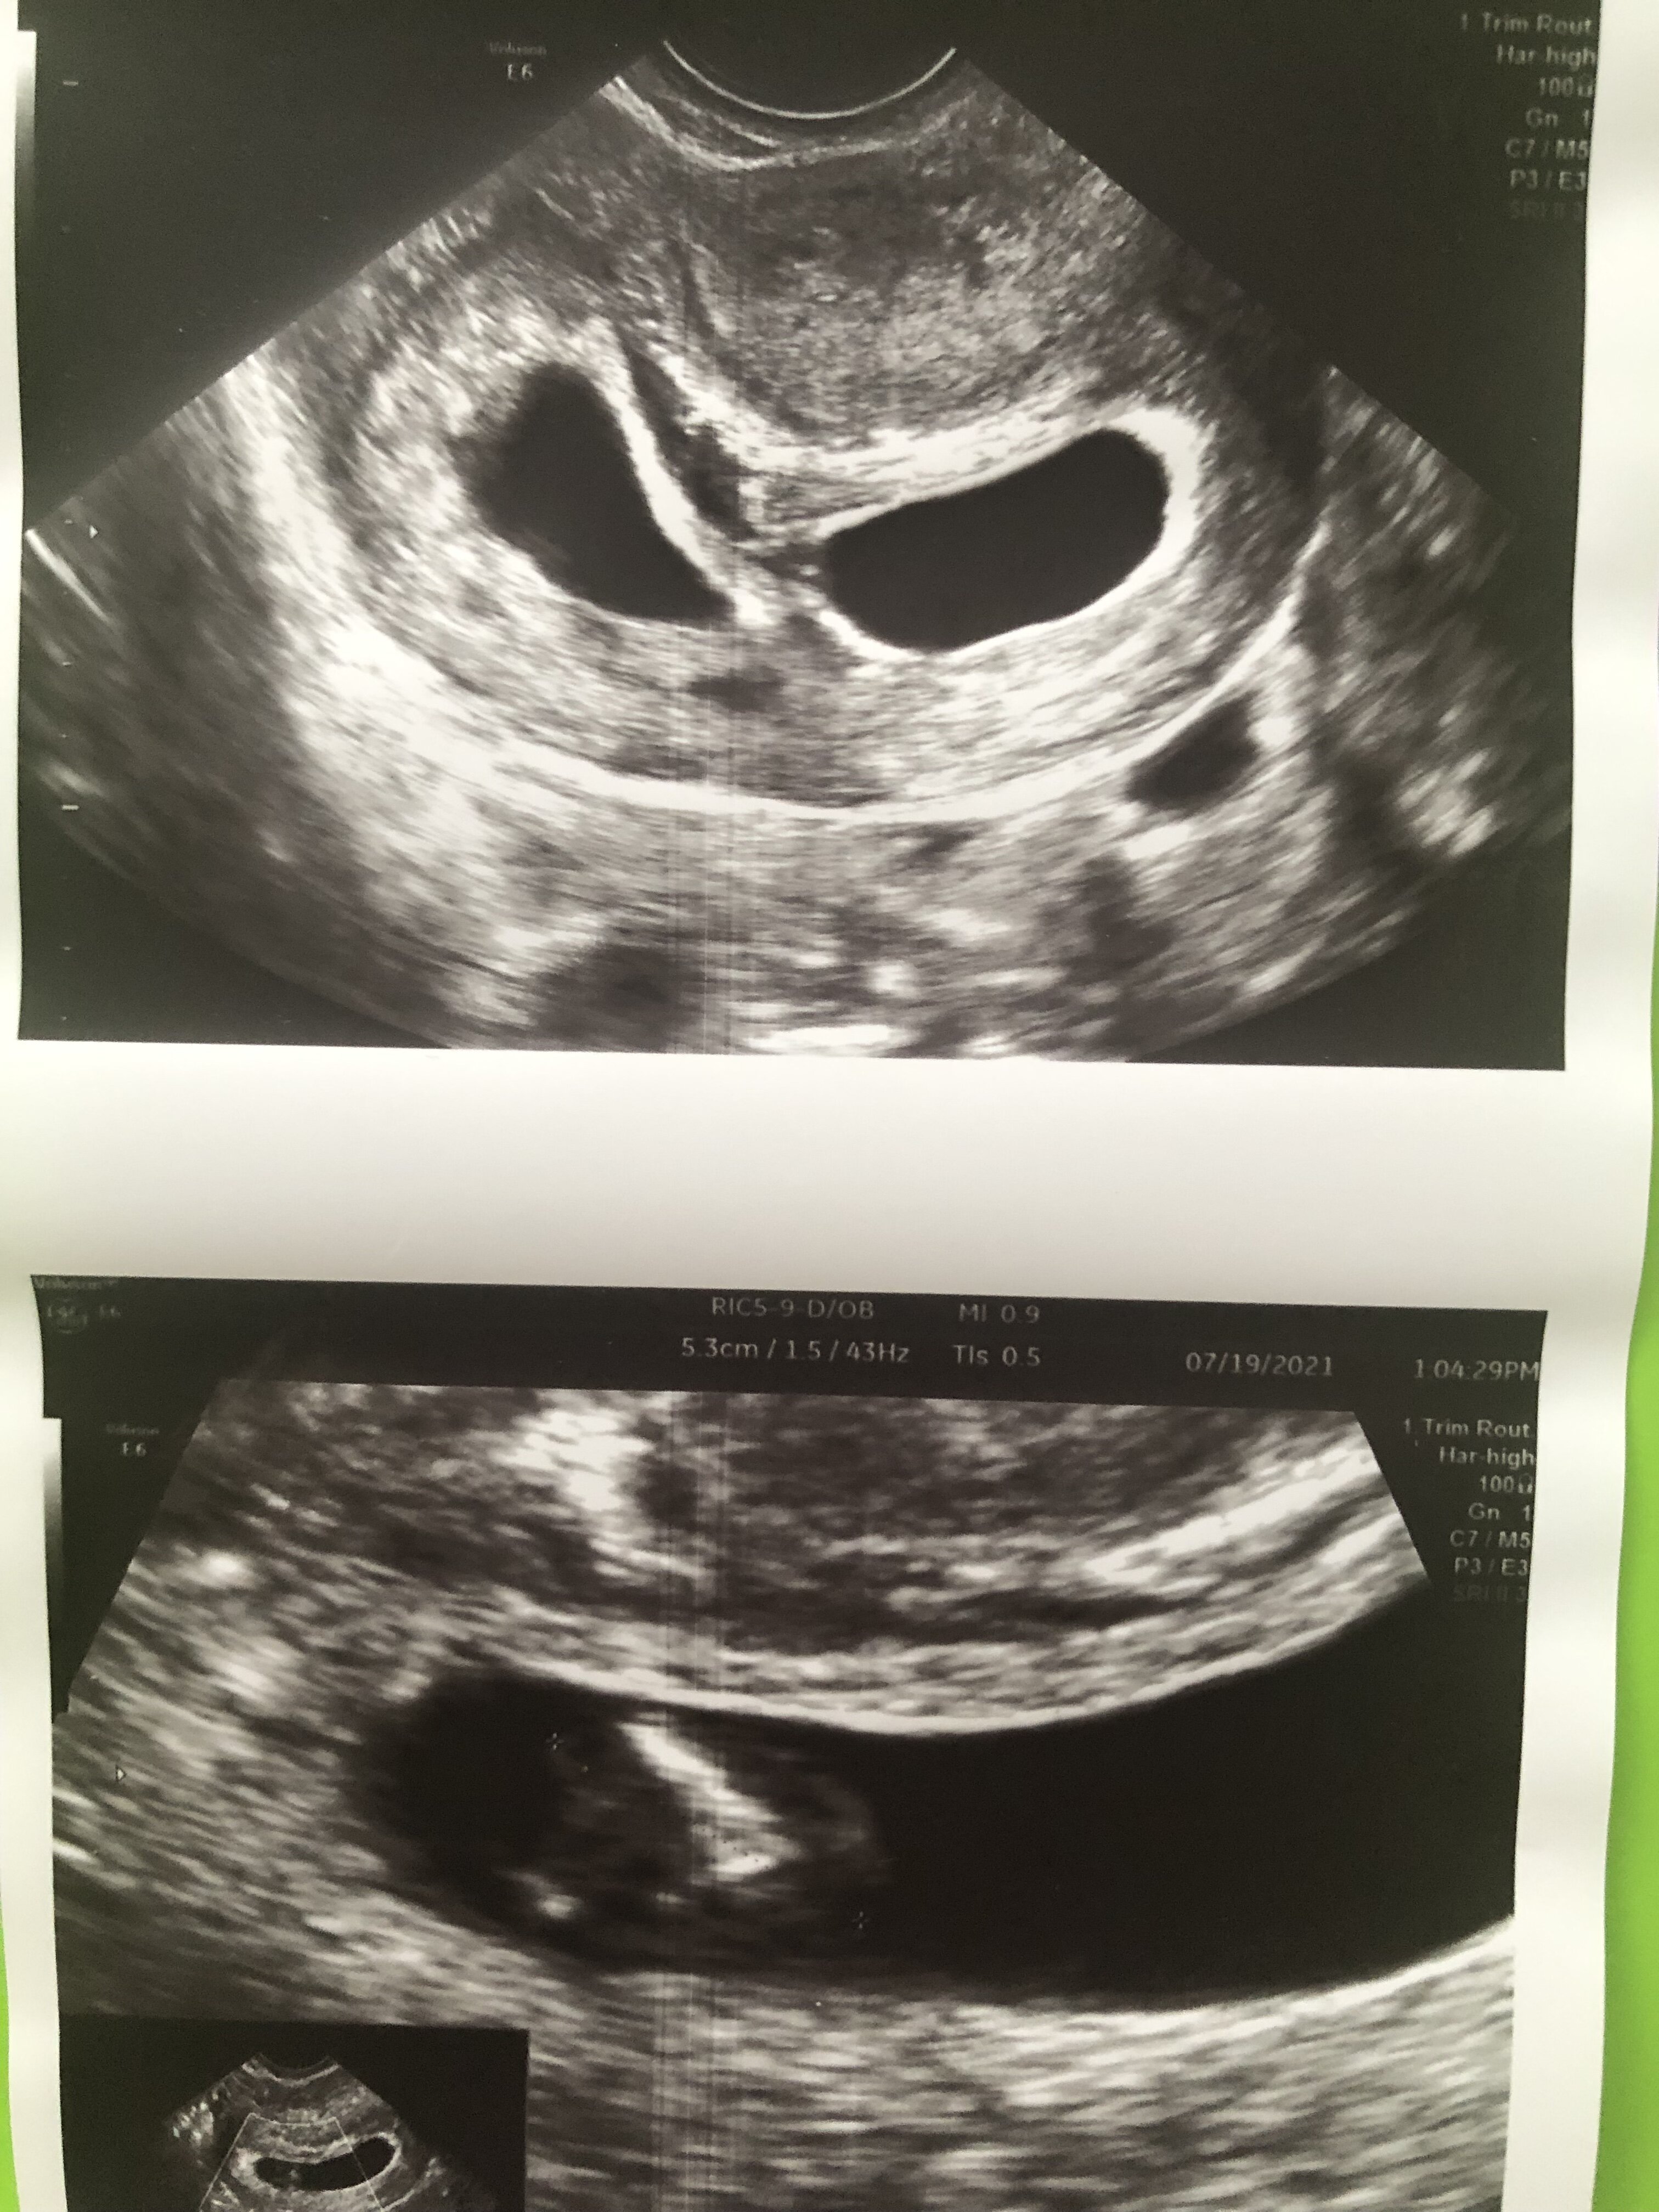

No a mi powiedział, że może być bardzo cienka błonka i może nie być jej widać...ogólnie powiedział że nie powie mi póki nie będzie miał pewności. On taki bardzo konkretny jest. Wrzucam zdjęcie z USG

Na pewno to jednojajowa. Tylko oby okazało się, że dwuowodniowa [emoji3590]. U mnie dopiero koło 20 tygodnia inny lekarz zauważył błonę między moimi dziewczynami. Była po prostu tak cienka, że prawie niewidoczna. A tak to wszyscy mówili, że jednoowodniowa [emoji33]. Ale nie martw się, będziesz miała często wizyty i jakby coś działo się złego, to od razu zareagują [emoji4][emoji2296]